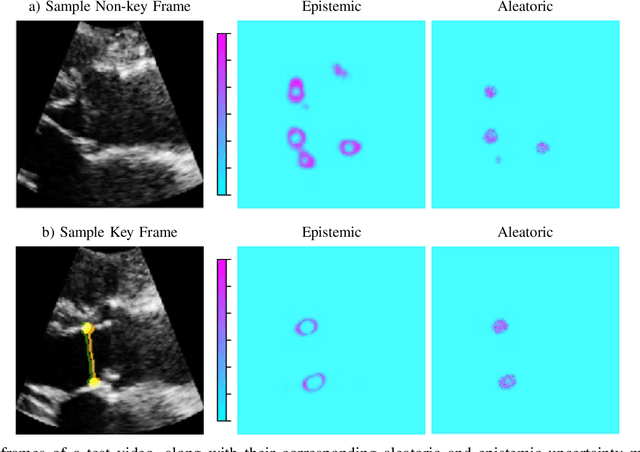

Abstract:This paper presents U-LanD, a framework for joint detection of key frames and landmarks in videos. We tackle a specifically challenging problem, where training labels are noisy and highly sparse. U-LanD builds upon a pivotal observation: a deep Bayesian landmark detector solely trained on key video frames, has significantly lower predictive uncertainty on those frames vs. other frames in videos. We use this observation as an unsupervised signal to automatically recognize key frames on which we detect landmarks. As a test-bed for our framework, we use ultrasound imaging videos of the heart, where sparse and noisy clinical labels are only available for a single frame in each video. Using data from 4,493 patients, we demonstrate that U-LanD can exceedingly outperform the state-of-the-art non-Bayesian counterpart by a noticeable absolute margin of 42% in R2 score, with almost no overhead imposed on the model size. Our approach is generic and can be potentially applied to other challenging data with noisy and sparse training labels.